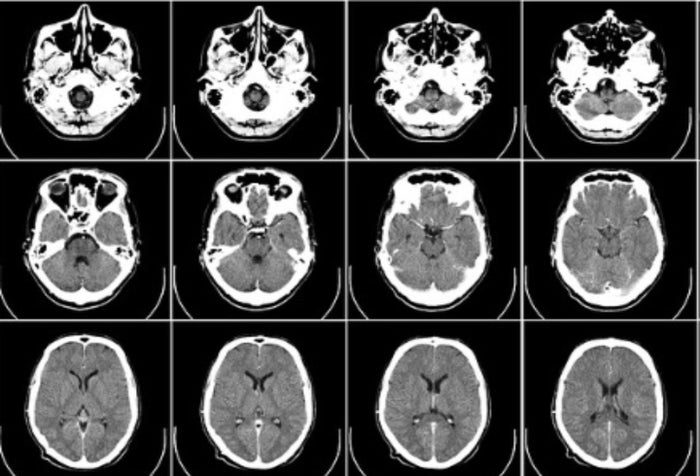

Imagen Referencial de uso libre- Pixabay

En la clínica fue canalizada y medicada para el dolor de cabeza ya que, asegura, “sentía que algo se me desgarraba”; sin embargo, allí no hubo más atención frente a qué estaría generando el incontrolable dolor y de paso las razones de la pérdida de visión en uno de sus ojos, “me dicen que no tenían la persona especializada y me trasladaron a la Clínica Roma, pero allá también me dijeron que no contaban con los profesionales para este tema, por lo que fui trasladada a la Clínica de Occidente donde por fin me realizan un 'tac' que me dicen que no arrojó nada”.